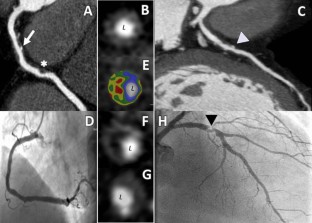

Fig. 2